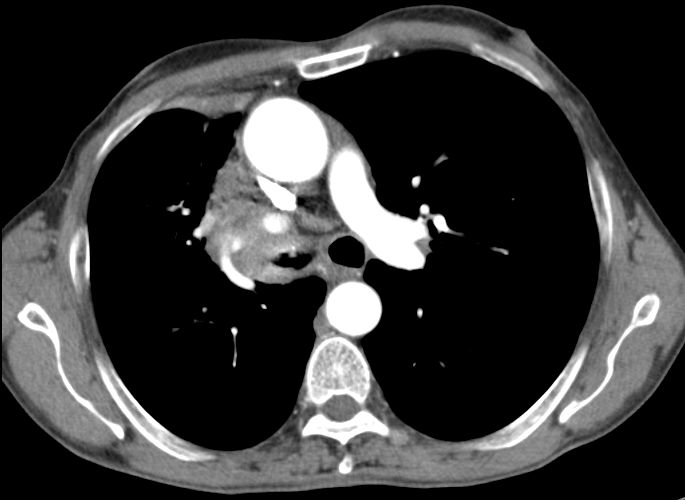

| Embolie | 55-jähriger Mann mit SCC rechts zentral mit

Verschluss der Mittellappens und Stenose des Zwischenbronchus T4 N2b Mo. Vom

Tumor eingeschlossen eine Pulmonalarterie mit einer kreisrunden Aussparung

durch einen Embolus.![]() | ||